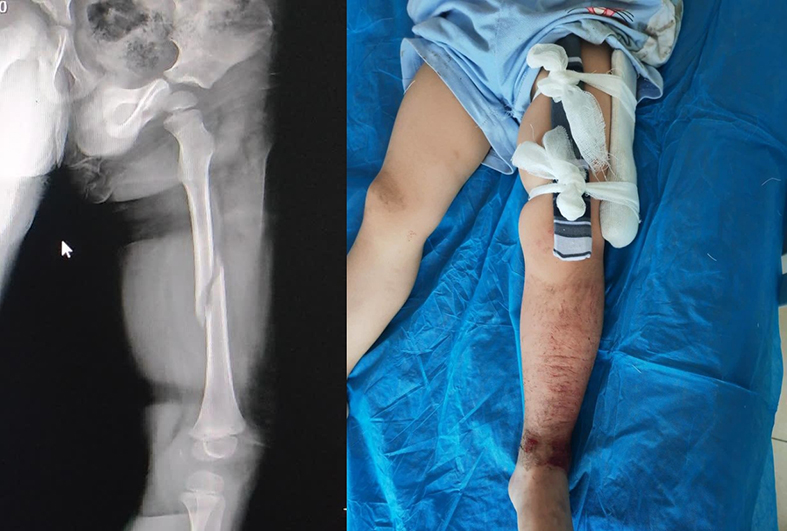

经相关检查,患者系左股骨干骨折。接到求助信息前来会诊的副院长、骨科副主任赵俊文介绍,股骨干骨折通常出血量很大,患者是3岁儿童,体内血液量本身较少,减少出血是必须考虑的问题。此外,还要考虑骨折愈合关节功能问题、骨骺生长问题。权衡再三,团队决定采用小切口复位微创弹性髓内钉内固定法为患者进行手术。

16时,麻醉科主任文爱平的保驾护航下,赵俊文站上手术台,将2枚直径为2.5mm的弹性髓内钉精准地置入患者股骨髓腔内完成复位和固定。经C型臂透视机检查,骨折断端对位对线良好,畸形纠正。手术用40多分钟完成,术中几乎无出血,为患者减轻了病痛,受到了患者家属的极大肯定。